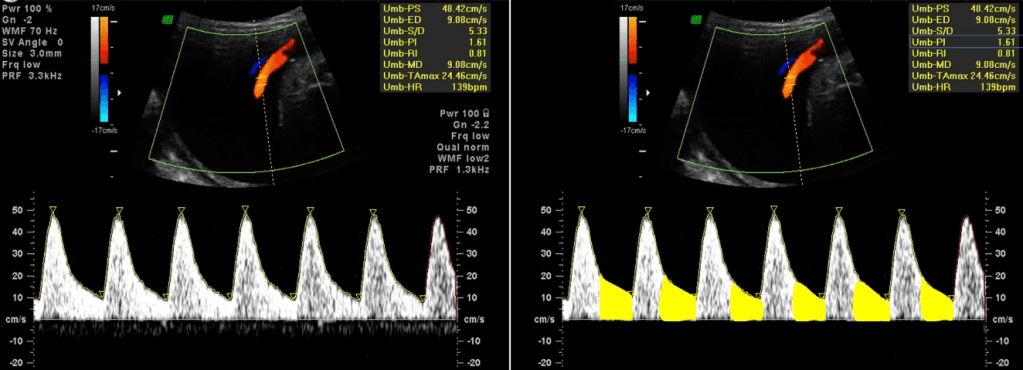

Artéria umbilical

A avaliação da artéria umbilical permite identificar alterações na resistência ao fluxo sanguíneo, que refletem o funcionamento da placenta.

Nesse contexto, utiliza-se o Doppler colorido para localizar as artérias e a veia umbilical, enquanto o Doppler espectral gera gráficos da velocidade do fluxo ao longo do tempo, permitindo calcular índices como o índice de pulsatilidade (IP), cujos valores de referência variam a depender da idade gestacional.

Alterações no desenvolvimento ou na função dos espaços intervilosos podem levar ao aumento dessa resistência ao fluxo sanguíneo nas artérias umbilicais, comprometendo a perfusão fetal.

Com a progressão da insuficiência útero-placentária, esse aumento torna-se mais severo, podendo reduzir ou até interromper o fluxo sanguíneo durante a diástole, caracterizando a chamada diástole zero.

Ademais, nos casos mais graves, observa-se a inversão do fluxo diastólico, conhecida como diástole reversa, indicando falência placentária avançada e maior risco de complicações fetais.